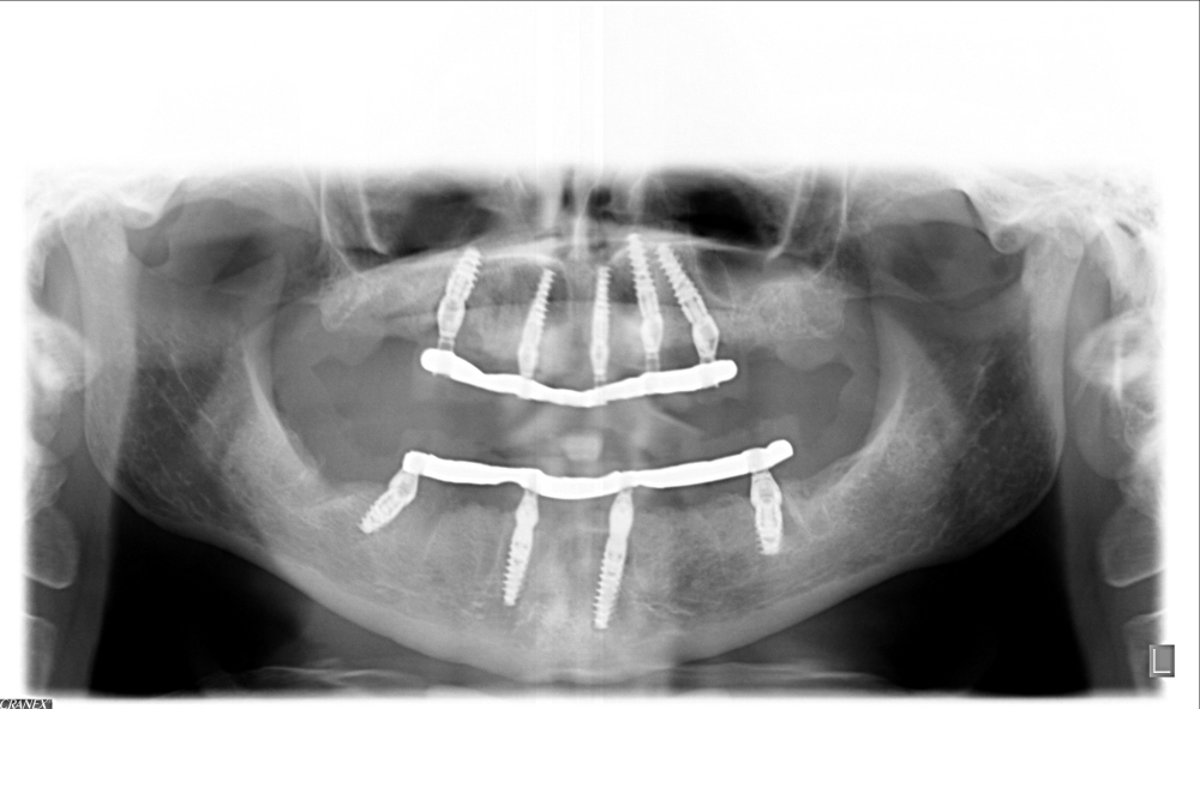

Dopo averle effettuato una radiografia panoramica e una TAC Cone Beam , siamo riusciti a individuare le aree di osso più favorevoli per l’inserimento degli impianti dentali.

Alla paziente, in sedazione cosciente, sono stati rimossi tutti i denti dell’arcata superiore e posizionati direttamente negli alveoli post-estrattivi (le cavità rimaste dopo la rimozione dei denti) 5 impianti dentali seguendo il protocollo di carico immediato post-estrattivo da anni sviluppato nella nostra Clinica.

Dopo una settimana, con la rimozione dei denti e l’inserimento contemporaneo di 4 impianti dentali nella mandibola, è stata riabilitata anche l’arcata inferiore seguendo il medesimo protocollo di Implantologia Estetica Immediata OnlyOne® che prevede, come detto, la fuoriuscita dei denti dalle gengive naturali.